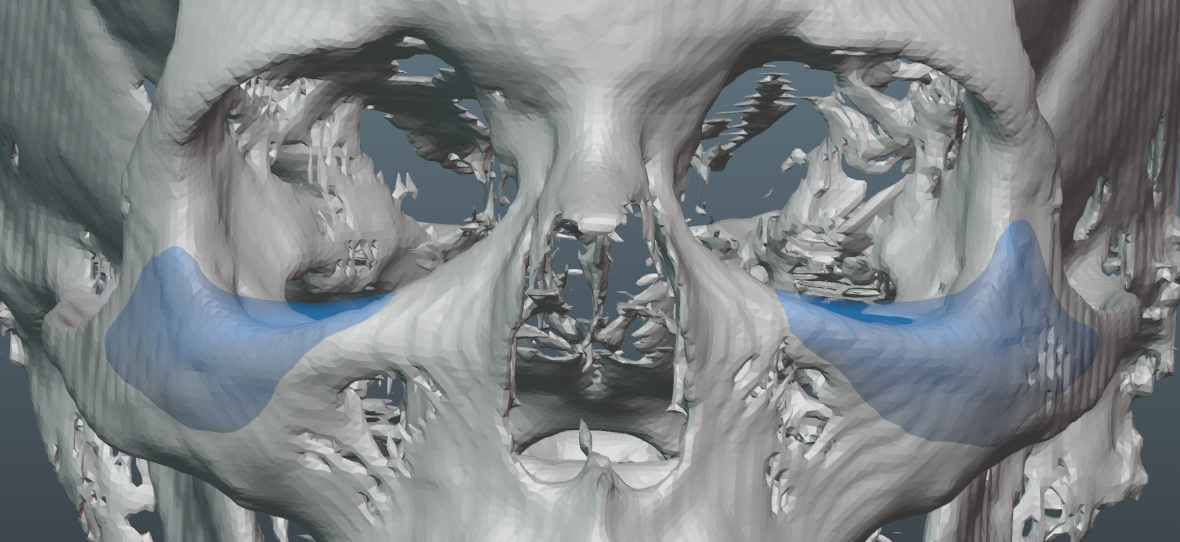

-Patient also desired more volume around the infras and malars.

-Already had nice eye area, with good soft tissue distribution.

-Infra rim shape has a slight, but improved, curve to keep a natural look.

-Patient also desired more volume around the infras and malars.

-Already had nice eye area, with good soft tissue distribution.

-Infra rim shape has a slight, but improved, curve to keep a natural look.